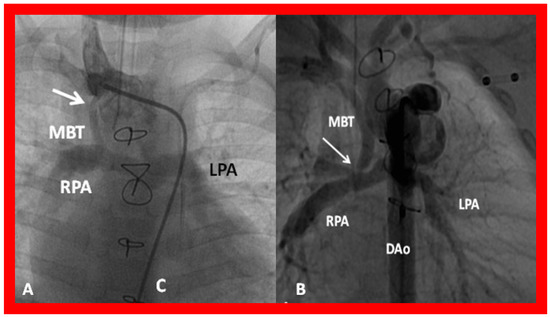

Angiographic counter parts of both the palliative procedures are shown in Figure 24, to have better comprehension of the anatomy of these procedures.

Figure 24. Selected cine frames in postero–anterior (a) and lateral (b) views, demonstrating a Blalock–Taussig (BT) shunt (arrow in a) to care for infants with decreased pulmonary blood flow (a) and pulmonary artery banding (PB) (arrow in (b)) in babies with increased pulmonary blood flow (b), respectively, during Stage I of Fontan procedure. C, catheter; LPA, left pulmonary artery; RPA, right pulmonary artery. Neonates with adequate pulmonary blood flow do not need any intervention and can go directly to Stage II at about the age of 3 months. Reproduced from Rao PS, Indian J Pediatr 2015;82:1147–1156 [36].